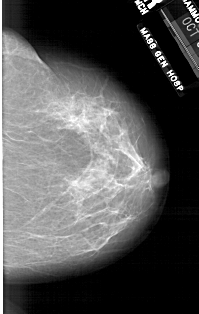

A_1760_1.LEFT_CC

LEFT_CC LINES 6601 PIXELS_PER_LINE 3826 BITS_PER_PIXEL 12 RESOLUTION 43.5 OVERLAY